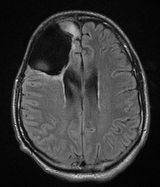

Georgetown Lombardi Kapsamlı Kanser Merkezi araştırmacıları, löseminin bir türünde FDA tarafından onaylanmış arsenik bazlı bir tedavinin, tedavisi zor bir başka kanser türü olan Ewing Sarkoması’nda (ES) yararlı olabileceğini keşfetti. Hayvan modellerinde yapılan çalışma, yüksek düzeyde malignant pediatrik beyin kanseri olan medulloblastomun tedavisinde de arsenik kullanımının yararlı olabileceğini ortaya koydu.

Çalışmanın sonuçları geçtiğimiz ay Journal of Clinical Investigation’da yayımlandı. Araştırmacılar, yıllar süren bu çalışmada, inceledikleri tümörlerde, hedgehog/GL11 adı verilen bir yolak keşfetti. İlerleyen zamanlarda ise, arsenik trioksit (Trisenox®) tedavisinin ES ve medulloblastomda bu yolağı tamamen kapattığını gördü. Çalışmanın baş araştırmacısı Doç. Dr. Aykut Üren, bu yolağın kolon, pankreas ve bazal hücreli cilt kanseri ve başka kanser türlerinde de mevcut olduğunu; FDA tarafından onaylanmış bu ilacın başka kanser türlerinde de test edilebileceğini belirtti.

Dr. Üren, kemoterapide olduğu gibi arseniğin yüksek dozlarının toksik olabilirken, düşük dozlarının kanser tedavisinde kullanılabileceğini belirtiyor. 2009 yılında Dr. Üren ve ekibi, hedgehog/GL11 yolağının ES’de aktive olduğunu keşfetmişti. Bu ekip, ES’de arsenik trioksit ile yolağı inhibe eden ve aynı zamanda medulloblastomda arseniğin etkinliğini gösteren ilk araştırma ekibi unvanını taşıyor. Çalışma  National Institutes of Health, the Children’s Cancer Foundation of Baltimore ve Accelerate Brain Cancer Cure tarafından finanse edildi.